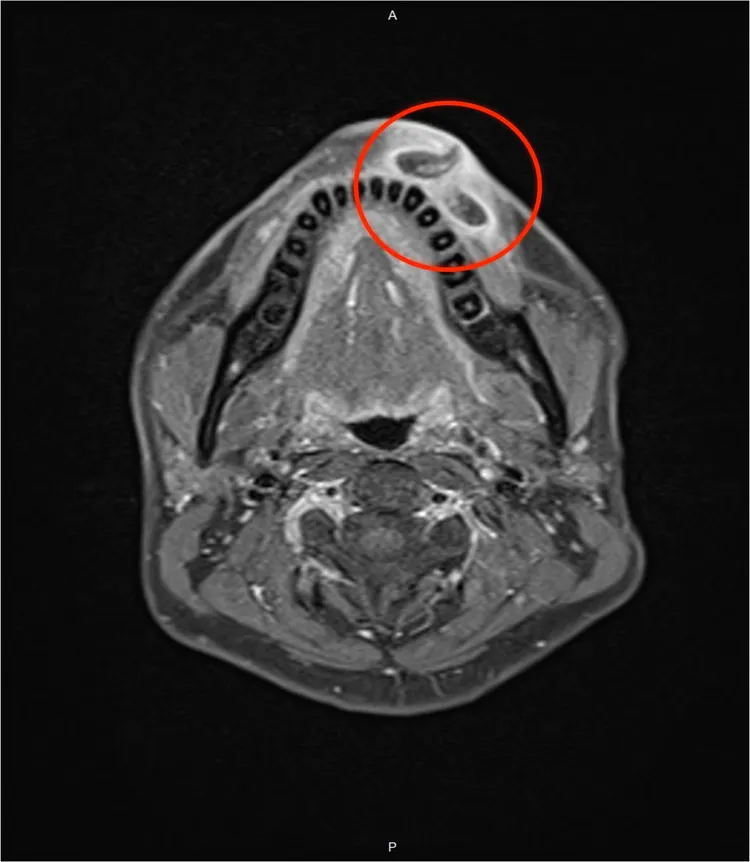

醫師進一步替陳先生安排核磁共振影像檢查,結果證實有蟲,因嘴唇周圍有大血管,蟲體為躲避容易碰撞造成出血,醫師曾在門診嘗試替陳先生夾出蟲,但病人痛到受不了,只好改採全身麻醉,在手術室成功活捉3隻寄生於嘴唇上的蟲,手術時間約15分鐘,陳先生術後住院一晚確認恢復良好才出院。

馬偕醫院將取出後的蟲體分別送病理檢驗,以及台灣大學昆蟲系系統分類研究室蕭旭峰教授鑑別,確認是台灣少見的馬蠅幼蟲。劉崇基表示,從陳先生嘴唇取出的馬蠅幼蟲,平均2.5公分長、0.8-1公分粗。